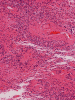

Pathology of the Case: MRI shows a large mass with the more solid component located in the lateral ventricles and the cystic component protruding into the cortical area. The solid area is enhanced (Panel A). On low magnification, the lesion has alternating area of high and low cellularity (Panel B) with scattered calcifications in some of the sections. Medium and high magnification demonstrates perivascular coronary arrangement of cytoplasmic processes (Panel C, D, and E). The nuclei are bland and mitotic figures are not readily seen. Randomly scattered brown pigment containing cells are found in multiple areas of the tumor (Panel F, G, and H). Scant lipidized cells with enlarged nuclei (Panel I) are also present. The tumor cells are strongly positive for glial fibrillary acidic protein (GFAP) (Panel J and K) and S100 protein but are negative for epithelial membrane antigen (EMA), neurofilament proteins, and NeuN. The overall Ki67 labeling is low but focal small areas (about the size of one high power field) has increased labeling. The pigment appears to be melanin on microscopic examination. These pigments are positive with Fontana-Masson stain (Panel L) but negative for Prussian blue stain for iron (Panel M). These features confirmed that these are melanin pigments. The pigment granules are positive for periodic acid-Schiff reaction (N), negative for Ziehl-Neelsen (acid fast) stain..